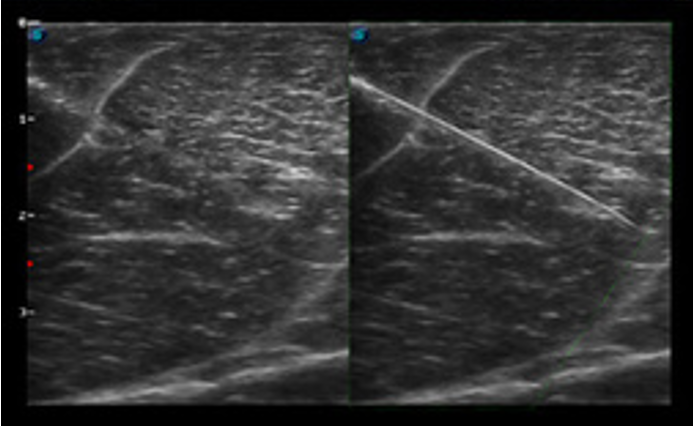

Ultrasound-guided procedures such as fine-needle aspiration (FNA), fluid drainage, and catheter placement increase safety and success rates.